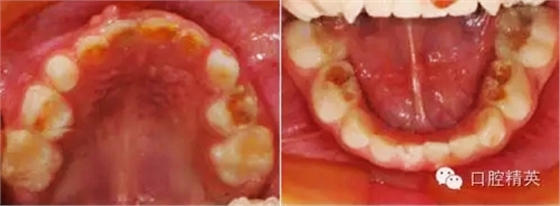

臨床檢查:頜面部及頸部未見明顯異常??谇恍l(wèi)生狀況尚可, 52,61,62,63,73唇舌面齲,54,64,74,84牙合面齲壞,腐質(zhì)中等,叩(-),松(-),牙齦未見明顯異常;75牙合面深齲壞,大量軟腐,叩(-),松(-),牙齦未見明顯異常,腐質(zhì)未去凈見露髓孔;51大面積齲壞,大量腐質(zhì),叩(+),松(Ⅰ),唇側(cè)牙齦可見5mm×6mm的包,軟;余牙未見異常。

診斷:S-ECC